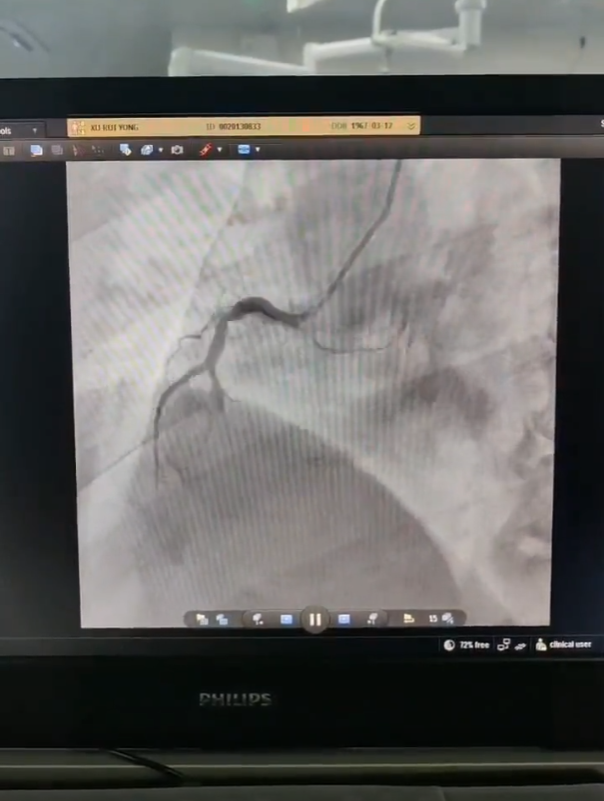

55岁的许先生家住王集镇李时村,3月9日12点20分突发胸痛不适,家人立即陪同到村卫生室就诊。12点39分,村卫生室工作人员利用心电仪采集心电图并上传到“心电一张网”,通过会诊后诊断结果为:急性心梗,情况非常紧急,随时可能出现生命危险。在我院专家指导下,村卫生室工作人员立即为许先生服用双联抗血小板药物,并开通绿色通道。14点整,120急救车通过绕行镇卫生院、县人民医院急诊室、监护室,急速将患者送达我院导管室开展介入治疗。

14点30分患者血管开通,经过30分钟的合力抢救,完成堵塞血管的进一步扩张并放入支架,15点整,手术结束,患者抢救成功。